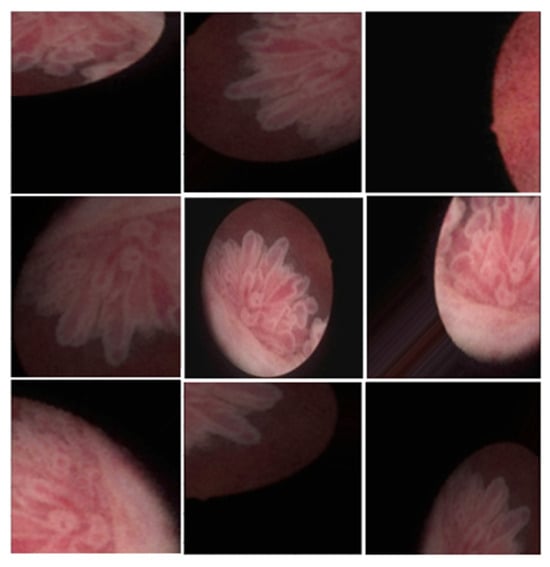

Figure 2.

Augmentation of cystoscope images; rotation, zooming, skewness, etc.

The dataset was split into training and validation sets in a 4:1 ratio. Data augmentation techniques, including rotation, zoom in/out, flipping (horizontal/vertical), and height/width shifts, were applied to the images in the dataset (Figure 2).